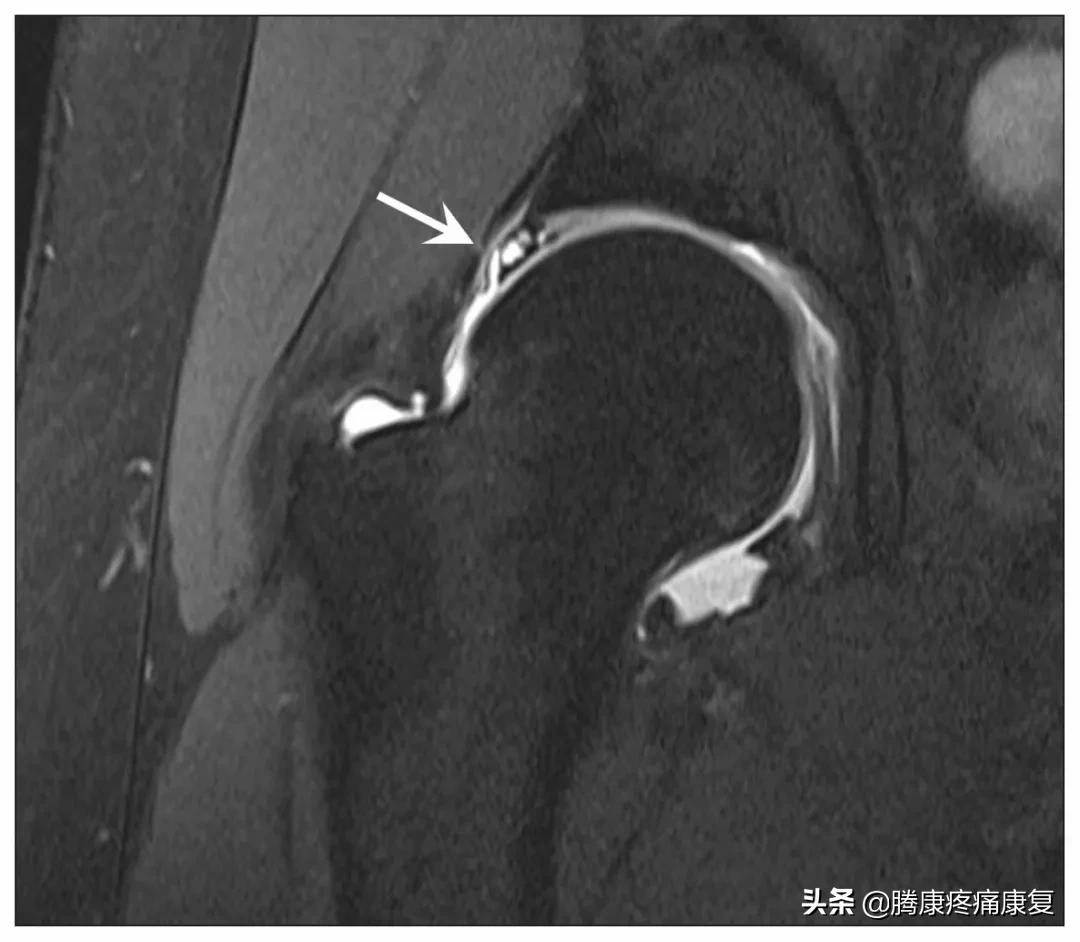

我们可以通过影像学检查,将这些其他情况相互区分,例如,X光可以显示骨关节炎的迹象,而MRI可以用来诊断肩唇撕裂。